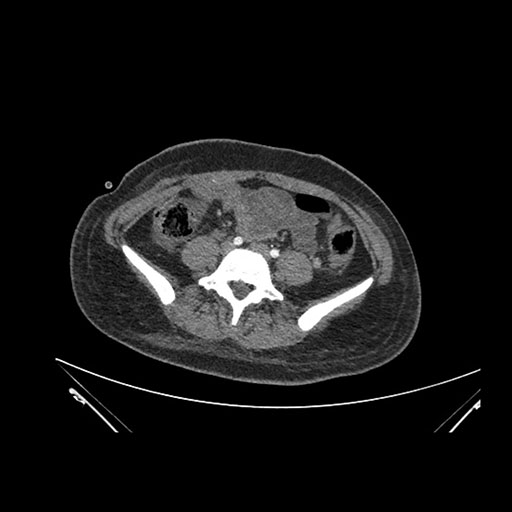

Axial Arterial

Imaging analysis

Based on initial findings, which issue(s) would you be most concerned about?